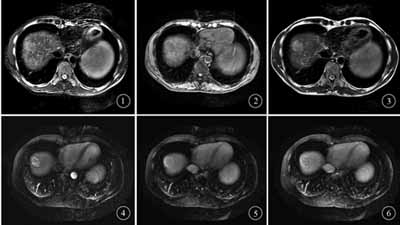

16例SHCC共检出癌灶21个,其中肝右叶18个,左叶3个,癌灶1.2~1.5 cm 2个,1.6~2.0 cm 5个,2.1~3.0 cm 14个。MRI平扫病灶T1WI低信号17个,等信号1个,高信号3个。Gd-DTPA动态增强扫描富血供病灶17个,动脉期明显强化,门静脉期退出,时间—信号曲线呈速升速降型,典型病例图像见图1~6;乏血供病灶4个,动脉期门静脉期未见明显强化,延迟期轻度强化,时间—信号曲线为缓慢上升型。对平扫及Gd-DTPA动态增强对肝癌病灶的确诊率结果,见表2。MRI平扫及Gd-DTPA动态增强对假包膜的检出情况,见表3。

图1 平扫T2WI脂肪抑制序列可见肝右叶高信号灶 图2 平扫T1WI肝右叶病灶呈低信号 图3 平扫T2WI肝右叶病灶呈高信号 图4 动态增强扫描动脉期病灶明显强化 图5 动态增强扫描门静脉期病灶强化程度下降 图6 动态增强扫描延迟期可见病灶周围假包膜